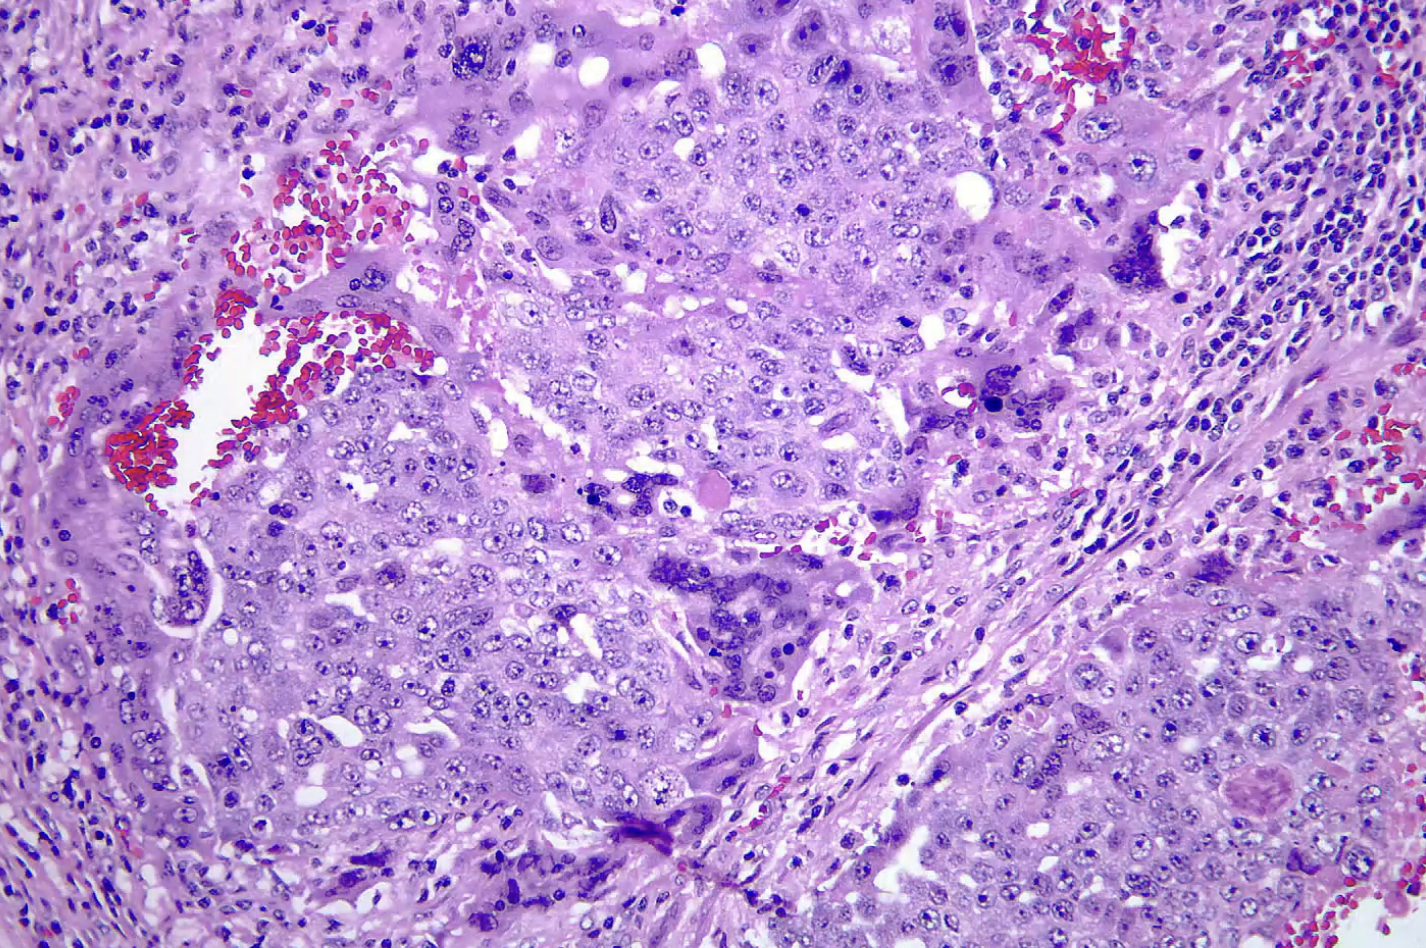

Embryonal Carcinoma - puberty to age 30 worse prognosis than seminoma

Embyronal Carcinoma

Embryonal Carcinoma